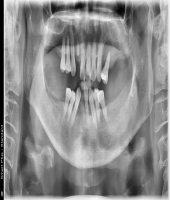

| ● 진료과목 : [임플란트] 치주환자의 임플란트 보철치료

| ● 내용 : 50대 치주환자의 임플란트치료. |